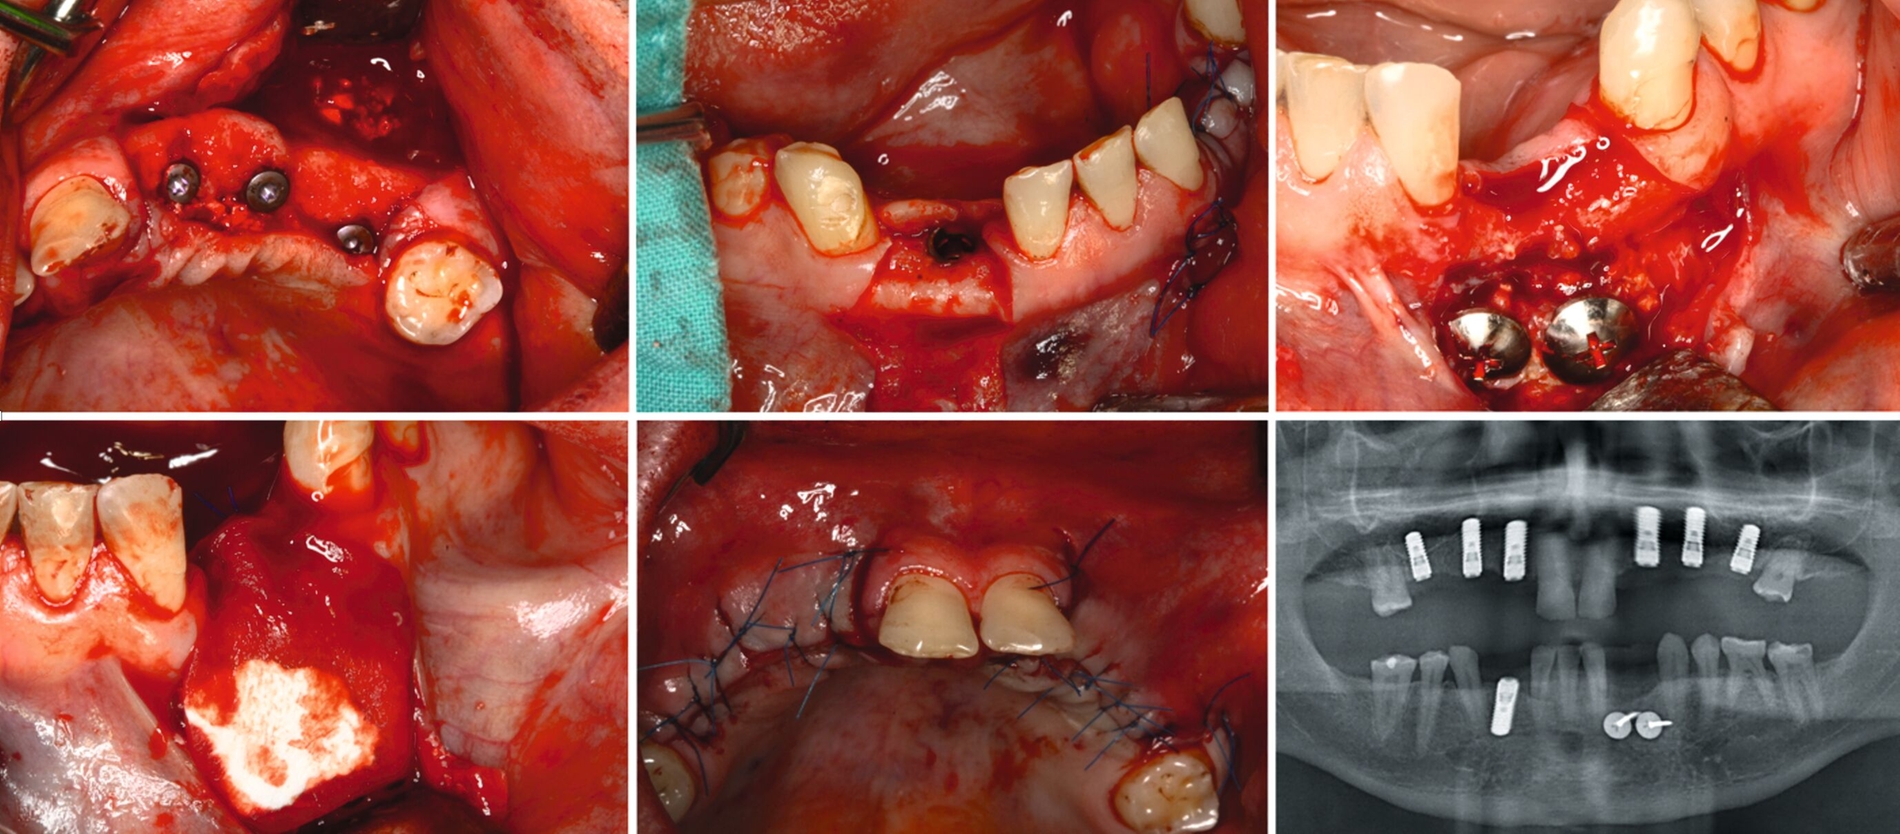

Unter intravenöser Sedierung wurden Implantate im Ober- und Unterkiefer inseriert, kombiniert mit Sinusbodenelevation und vestibulären Augmentationen. Aufgrund unzureichender Knochenverhältnisse erfolgte an Regio 33 eine zweizeitige augmentative Maßnahme mit Schirmschrauben und Membran (Abbildung 6), gefolgt von der sekundären Implantation nach vier Monaten (Abbildung 7).

Nach komplikationsfreiem Heilungsverlauf (Abbildung 8) erfolgte die Freilegung der Implantate, die Einsetzung von Gingivaformern und die Anpassung des Interimsersatzes (Abbildung 9). Wegen der dadurch anfallenden zusätzlichen Kosten verzichtete der Patient auf ein Langzeitprovisorium.